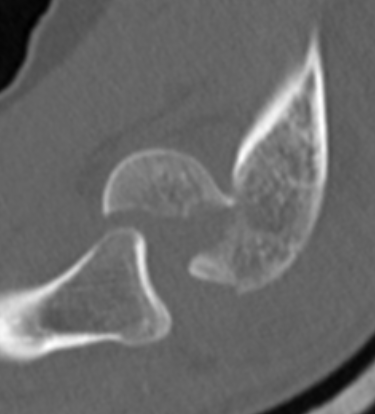

Coronal shear fracture of the distal humerus

Capitellum +/- trochlea

Bryan & Morrey Classification

| Type I | Type II |

|

Large osseous fracture of the capitellum

Articular cartilage injury with little bone |

Hanh Steinthal fracture

Kocher Lorenz fracture |